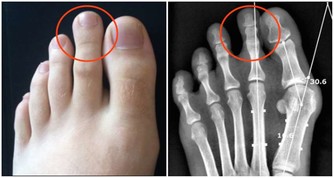

礦物質是對抗蛀牙的關鍵。當牙齒琺瑯質變弱,就失去礦物質的含量。補充流失礦物質的最好辦法(除了食用富含礦物質的食物以外)就是使用礦化牙膏。這就是為什麼許多市售的牙膏都含有氟的成分,它能夠促進牙齒琺瑯的健康。